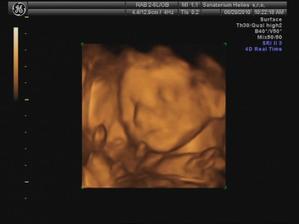

29.6. jdeme na 3D ultrazvuk 🙂 těšíme se... - bylo to úžasný 🙂 cena sice vyšší, ale jedna barevná fotka tištěná, 3 fotky na mail a téměř půlhodinové video, ze kterého jsme si doma udělali ještě asi 120 fotek 🙂